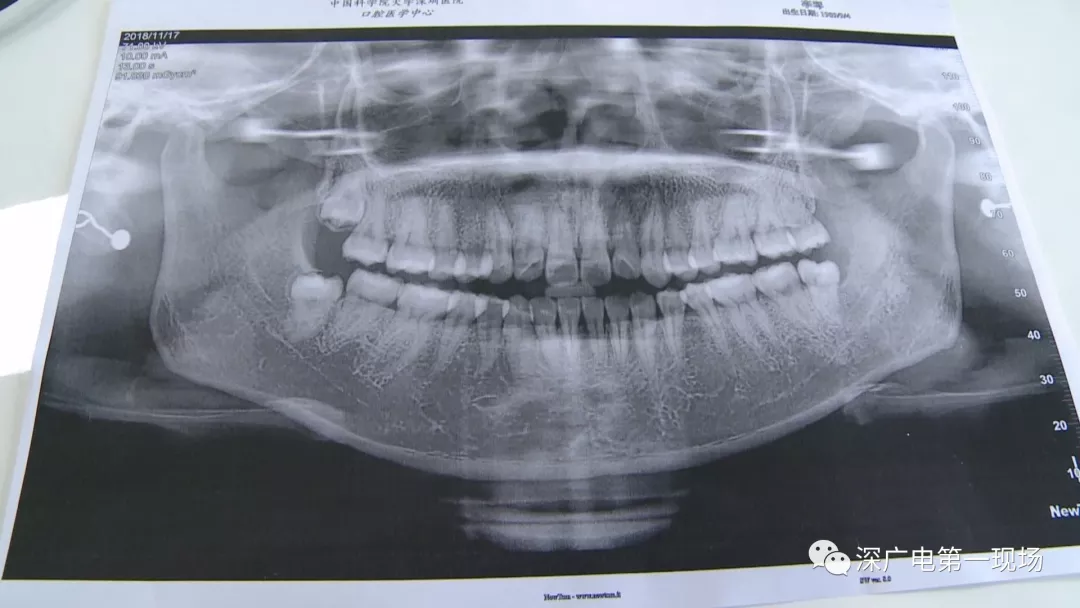

針對李女士的情況,醫(yī)生介紹,當(dāng)時(shí)要想拔出李女士的這顆智齒,難度還是很大的,屬于復(fù)雜智齒的拔除術(shù)。她的風(fēng)險(xiǎn)在于距離神經(jīng)管近,同時(shí)這顆牙齒完全埋在牙床最后的位置,直接往外拔,會加大頜骨的風(fēng)險(xiǎn),因此需要先切開,讓牙齒暴露后,切小再慢慢地拔出。